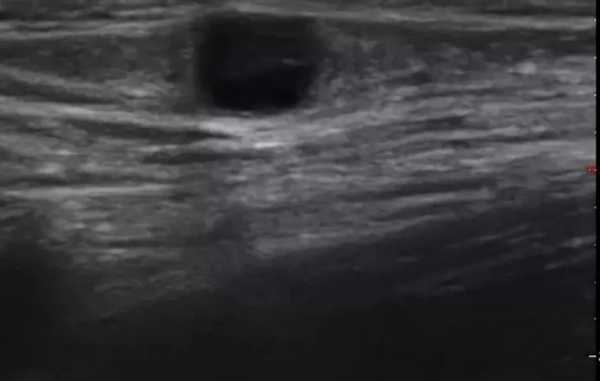

Паховые лимфоузлы на УЗИ